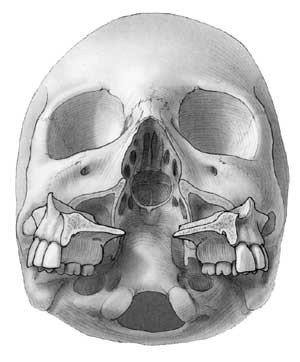

De siste tiårs etablering av multidisiplinære kraniofacialteam og transfaciale teknikker har gitt kirurgisk tilgang til mediale deler av hjernens basis og stamme fra sella turcica og ned til 4. halsvirvel (fig 1). Mens en transnasal, transsfenoidal tilgang vil være velegnet for lesjoner nær sella turcica (6), vil man ofte velge en transmaksillær, transfaryngeal tilgang for lesjoner i clivusområdet (7, 8) transoralt for lesjoner nær kraniocervikalovergangen (9) og endog transmandibulært for lesjoner kaudalt for dette (7).

Operasjonen innledes ved en midtlinjeincisjon gjennom alle bløtvevslagene i den harde og bløte gane. Deretter gjøres en standard LeFort I-maksillotomi, med vestibulær incisjon fra premolar til premolar på hver side (fig 4), horisontal osteotomi og nedfrakturering av maxilla. Maxilla spaltes deretter i to og roteres så forsiktig nedad og utad, hvoretter man har full eksponering av skallebasis, fra sella turcica og ned til atlasbuens forside (fig 5).

Under mikroskop åpnes deretter svelgveggen ved en midtlinjeincisjon gjennom alle lagene. Den beinete bakveggen fridissekeres subperiostalt, og ved bruk av høyhastighetsdrill fjernes deler av skallebasis i ønsket omfang inntil man kommer inn mot dura (fig 1).

De siste tiårs utvikling av multidisiplinære kraniofacialteam har gjort det mulig å angripe lesjoner beliggende i de sentrale, mediale sonene av skallens basis i fremre og midtre skallegrop nedenfra via transfaciale tilganger (fig 1). Vi har presentert to pasienter med svulster i clivus som ble operert ved hjelp av slike teknikker.